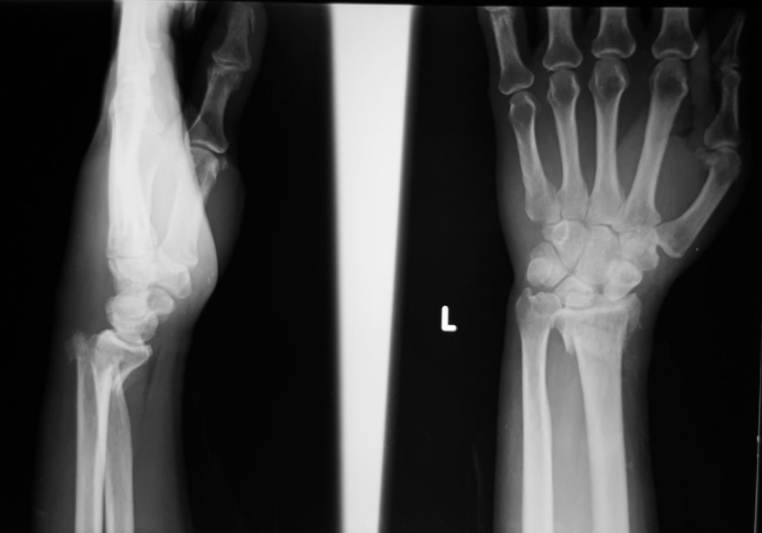

Monteggia

Forearm injury involving a fracture of the proximal third of the ulna with concurrent radial head dislocation, which is more common in children than adults.

Monteggia fractures are typically the result of a fall onto an outstretched hand, or more frequently a trauma. A classic mechanism is called the night-stick fracture, which produces the fracture when a patient guards against a strike using the ulnar side of their forearm.

Patients with a Monteggia fracture will present with pain and swelling at the elbow joint, which may or may not show obvious dislocation.

Most Monteggia fractures in children are treated with a cast, but most adults are treated surgically.

A major complication of Monteggia fractures is compartment syndrome, which is a rise in intracompartmental pressure that impedes blood flow.

Galeazzi

Forearm injury involving fracture of the distal third of the radial shaft with concurrent disruption of the distal radioulnar ligament.

Galeazzi fractures usually occur due to direct trauma or a fall onto an outstretched, pronated forearm.

A Galeazzi fracture presents with pain, swelling, and visual deformity of the distal forearm.

Because of the instability of a Galeazzi fracture, they are treated surgically to reduce the radius and with casting to keep the distal radioulnar joint reduced.

As with Monteggia fractures, the traumatic nature of this fracture puts patients at risk of compartment syndrome.